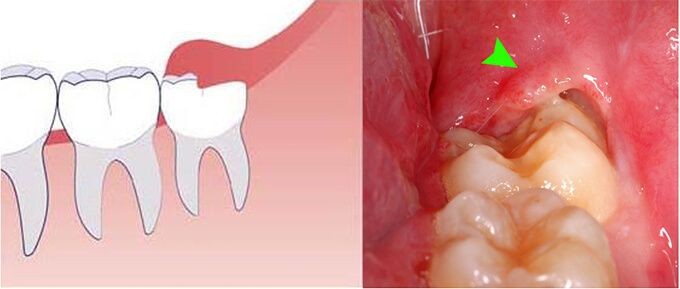

Viêm lợi trùm răng khôn có thể hình thành khi răng khôn chỉ nhú 1 phần (đâm thủng nướu). Sự phát triển mô mềm trên chiếc răng khôn đã mọc 1 phần được gọi là túi lợi, tạo điều kiện cho vi khuẩn trú ngụ, tăng sinh và gây bệnh nhiễm trùng, sưng tấy tại chỗ rồi sẽ lan rộng sau đó.

Trong một số trường hợp nghiêm trọng, tình trạng sưng tấy và nhiễm trùng trong viêm lợi trùm răng nói chung, viêm lợi trùm lên răng khôn nói riêng có thể kéo dài ra khỏi hàm đến má, cổ.

Nhận biết sớm khi bị viêm lợi trùm

Các triệu chứng của tình trạng viêm lợi trùm có thể xảy ra ở dạng cấp tính hoặc mạn tính trong thời gian dài. Có một số dấu hiệu giúp nhận biết tình trạng viêm lợi trùm, bao gồm:

• Lợi sưng đỏ: Phần lợi trùm trên phần mọc răng khôn bị sưng phồng và tấy đỏ. Khi ấn vào phần lợi trùm, sẽ thấy đau đớn. Có thể thấy chảy nước và mủ.

• Đau răng: Đối với tình trạng lợi trùm bị viêm có mủ, bạn sẽ cảm nhận thấy những cơn đau ở răng. Cảm giác đau sẽ kéo dài, thậm chí nuốt nước bọt hay há miệng đều đau điếng. Lợi trùm khi bị viêm nặng sẽ gây viêm ảnh hưởng quanh thân răng và hàm.

• Sốt và nổi hạch: Khi lợi trùm bị viêm và có mủ, có thể gây sốt. Phần góc hàm bị sưng và có xuất hiện hạch ở vùng cổ. Đây là những biểu hiện chứng tỏ sự viêm nhiễm.

• Chảy nước miếng: Lợi trùm bị viêm và sưng to sẽ gây khó ngậm miệng như bình thường. Khi đi ngủ có thể xuất hiện tình trạng nước miếng bị chảy ra và có mùi hôi khó chịu.

viêm lợi trùm

Lợi trùm răng bị sưng đỏ, gây đau rát và chảy nước miếng nhiều